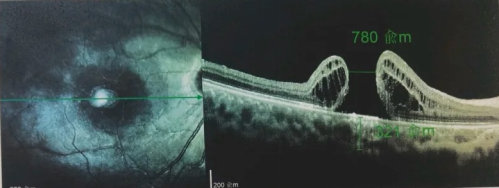

由于自身患有頸椎病,每次術(shù)后長(zhǎng)期的趴睡都讓他痛苦不堪。為了尋求更好的治療,吳爺爺來(lái)到廈門大學(xué)附屬?gòu)B門眼科中心,找到了眼外傷及眼底病2科的李海波博士后。此時(shí),吳爺爺右眼的黃斑裂孔已經(jīng)持續(xù)擴(kuò)大到780μm,演變?yōu)殡y治性的大裂孔。

最讓吳爺爺難以置信的是:術(shù)后只需保持平躺24小時(shí)!第二天復(fù)查時(shí),眼底鏡及OCT檢查清晰顯示——那個(gè)折磨了他大半年的大裂孔,竟然閉合了!且吳爺爺?shù)挠已垡暳τ辛嗣黠@的改善,術(shù)后3天已經(jīng)可以看到 0.15。